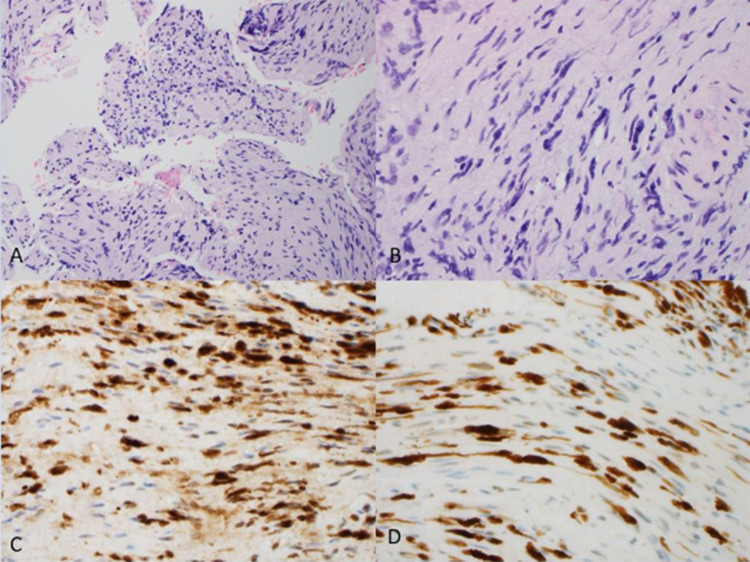

原发性颅神经淋巴瘤病(PCNL)是原发性中枢神经系统淋巴瘤(PCNSL)的一种罕见亚型,淋巴瘤浸润累及范围仅限于颅神经。在此,我们报告了一例成功进行基因组分析的 PCNL 病例。一名 57 岁的男性患者在诊断前经历了长达约 30 个月的漫长阶段,主要表现为通过类固醇治疗的多次颅神经痛。确诊时,患者右侧颅神经病变,累及颅神经(CN)V、VI 和 VII。右侧海绵状病变活检的病理结果与大 B 细胞淋巴瘤浸润神经纤维一致。患者的临床病程具有侵袭性和难治性,特点是病情无情发展,出现颈椎神经淋巴瘤病、脑脊液受累、脑外膜和脑实质内受累,尽管采用了多种疗法,包括化疗免疫疗法、布鲁顿酪氨酸激酶抑制剂、放射治疗、自体干细胞移植、嵌合抗原受体T细胞疗法(CAR-T)和全脑放射治疗。患者从最初诊断时起存活了22个月,在首次颅神经病变发作后存活了52个月。新一代测序发现了 PCNSL 中经常出现的突变(MYD88、CD79b 和 PIM1)。不寻常的发现包括涉及 PIM1 的总共 22 个突变,表明存在高度活跃的异常体细胞高突变和两个错义 CXCR4 突变。CXCR4突变从未在PCNSL中出现过,可能会对疾病生物学和治疗干预产生影响。我们通过文献综述来进一步阐明 PCNL。

Primary cranial neurolymphomatosis (PCNL) is a rare subtype of primary CNS lymphoma (PCNSL) in which infiltrative lymphomatous involvement is confined to cranial nerves. Here, we report a case of PCNL with successful genomic profiling. A 57-year-old male had a lengthy prediagnostic phase spanning approximately 30 months, characterized by multiple episodes of cranial neuropathies managed by steroids. At the time of diagnosis, the patient had right-sided cranial neuropathies involving cranial nerves (CN) V, VI, and VII. Pathological findings of the right cavernous lesion biopsy were consistent with large B-cell lymphoma-infiltrating nerve fibers. The clinical course was aggressive and refractory, characterized by relentless progression with the development of cervical spinal neurolymphomatosis, cerebrospinal fluid involvement, and ependymal and intraparenchymal cerebral involvement, despite multiple lines of therapy, including chemoimmunotherapy, Bruton's tyrosine kinase inhibitor, radiation, autologous stem cell transplant, chimeric antigen receptor T-cell therapy (CAR-T), and whole-brain radiation. The patient survived for 22 months from the time of the initial diagnosis and 52 months after the first episode of cranial neuropathy. Next-generation sequencing identified mutations (MYD88, CD79b, and PIM1) that are frequently observed in PCNSL. The unusual findings included a total of 22 mutations involving PIM1, indicating a highly active aberrant somatic hypermutation and two missense CXCR4 mutations. CXCR4 mutations have never been described in PCNSL and may have implications for disease biology and therapeutic interventions. We provide a literature review to further elucidate PCNL.